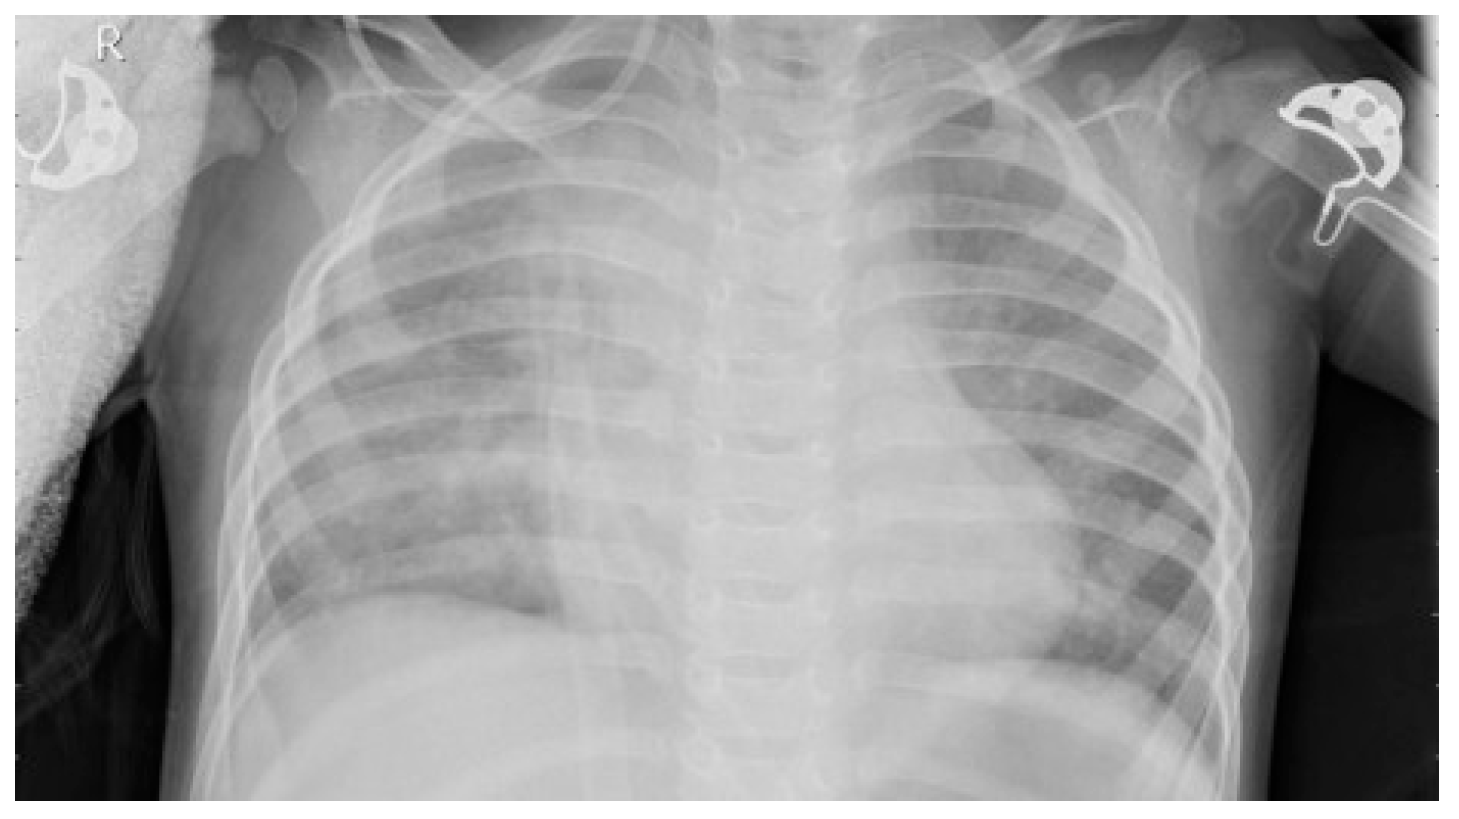

2.2. Dataset

2.4. Image Enhancement Techniques